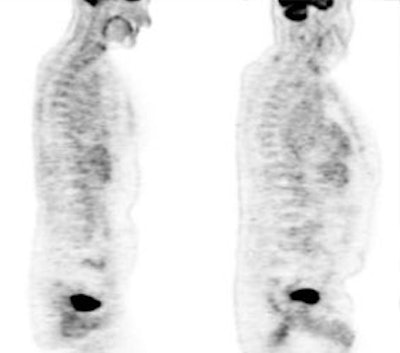

Hyperinsulinemia: The patient below had

a normal glucose level and was injected for an FDG PET

scan. Imaging revealed intense cardiac uptake and a large

about of muscular activity. The findings are consistent

with a hyperinsulinemic state and the patient subsequently

admitted to eating a small breakfast. |